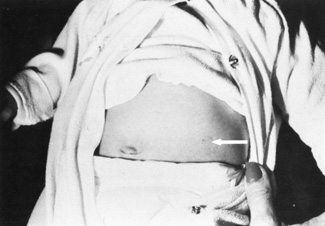

maternal age or prior history of an aneuploidy (see Fig. 2).  Fig. 2. Left midabdomen of neonate shows indented area probably resulting from

contact of the amniocentesis needle with the abdominal skin. Fig. 2. Left midabdomen of neonate shows indented area probably resulting from

contact of the amniocentesis needle with the abdominal skin.

| Needle injury rare (Fig. 2) |